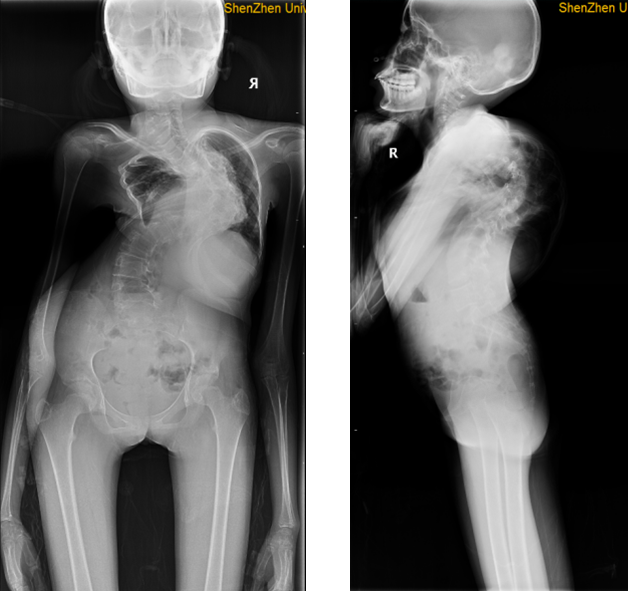

参加港大深圳医院脊柱畸形公益诊疗活动的共有120余名脊柱畸形患者,他们分别来自广东、广西、四川、云南、贵州、海南、湖南、湖北、河南、河北、江苏、江西、陕西、甘肃和香港等地,其中有80多位是从全国各地赶来就诊的新患者,也有40多位是陶惠人教授手术痊愈的老患者前来复诊。合并II型呼吸衰竭重度脊柱侧弯、双侧髋关节僵直的折叠人、合并脑瘫的极重度脊柱侧弯等多位患者在获得治疗后已自信回归正常生活。今年32岁的邹女士(化名)曾经差点放弃治疗,她是II型呼吸衰竭的极重度脊柱侧弯患者(FEV1(%)=17.5,BMI=12.9)。邹女士手术前影像图

手术风险极高,在陶惠人教授的坚持和专业治疗下,手术顺利且恢复良好,术后22个月的时候,邹女士顺利生育,母子平安。公益诊疗活动现场,张文智教授、陶惠人教授等脊柱外科专家团队为脊柱畸形患者免费制定个体化治疗策略,并根据他们的实际情况提供了专业的康复指导和建议。智善公益基金会为患者捐赠了脊柱全长正侧位X光片费用,并将10位申请救助的极重度脊柱畸形患者纳入捐赠范围,为他们分担部分手术费用。港大深圳医院骨科团队依托香港大学玛丽医院骨科,为脊柱疾病患者提供全方位服务,提供脊柱侧弯矫形手术、强直性脊柱炎后凸畸形截骨矫形手术、颈椎前后路手术、腰椎滑脱和椎管狭窄的手术治疗、脊柱感染和结核的综合治疗以及脊柱压缩性骨折和腰椎间盘突出症的微创治疗,团队与物理治疗科紧密联系,为患者康复提供完善、规范、专业的综合治疗。2024年1月,香港大学医学院人才引进陶惠人担任临床教授、顾问医生、港大深圳医院骨科医学中心主任、脊柱外科主任。陶惠人教授获深圳市政府特殊津贴,是深圳市高层次人才、2019深圳市卫生健康十大杰出贡献者,在国内外脊柱畸形矫治领域具有影响力。陶惠人教授在活动现场为小患者检查脊柱